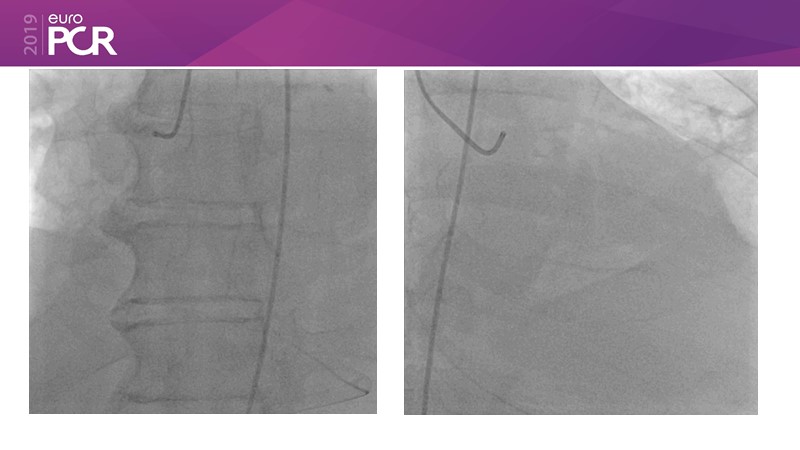

- To understand and discuss the need for a dedicated DES for diabetes mellitus (DM) and acute MI (AMI) patients

- To understand and learn benefits of DES+DCB strategy to provide uniform and homogenous drug delivery in patients with diabetes mellitus and acute MI